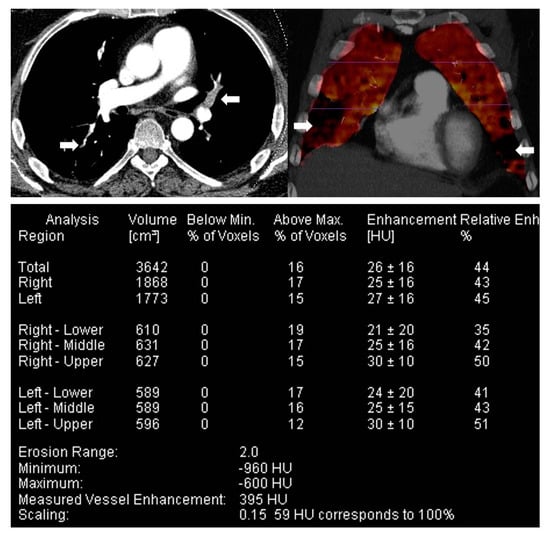

3.2. Dual Energy CT, DECT